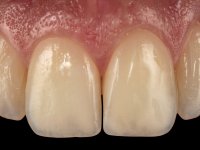

Paciente do sexo feminino, com 27 anos, não fumadora, apresentava uma restauração com resina composta tipo “Classe IV”, no angulo mesial do dente 2.1. A restauração não satisfazia esteticamente e fraturava com frequência. O bordo incisal do incisivo central direito e o remanescente natural do incisivo central esquerdo apresentava uma caracterização bastante marcada. Várias áreas de translucidez que tornariam a reabilitação bastante exigente sobre o ponto de vista técnico e estético. Na área da fratura não havia dentina exposta. A paciente gostava que a reabilitação tivesse uma abordagem o mais conservadora possível.

Realizou-se uma pré impressão em silicone para posteriormente ser feita uma restauração provisória em resina composta de polimerização “dual”. Seguidamente foi removida toda a restauração e realizado o preparo dentário. Este preparo consistiu na planificação do angulo dentário e na preparação ligeira da superfície palatina. A superfície palatina foi preparada para um assentamento sem interferências. Foi realizada uma impressão com dupla mistura e dupla viscosidade e de seguida foi feita uma restauração provisória em resina de polimerização “dual” sem qualquer tipo de adesão. Em laboratório, realizado o modelo de trabalho foi confecionada uma micro restauração de cerâmica feldespática. Essa peça de cerâmica utilizou essencialmente a superfície palatina mesial e o angulo incisal para se estabilizar. Na superfície vestibular a peça de cerâmica sobrepunha-se á superfície vestibular dentária em cerca de 2mm. Na clínica, a restauração provisória foi removida. A superfície dentária foi devidamente preparada e a micro restauração cerâmica depois de devidamente acondicionada foi colada no dente somente com adesivo. A superfície de cerâmica que sobrepunha a superfície dentária vestibular foi cuidadosamente eliminada. Para isso foi sendo feito o seu polimento de forma progressiva com discos e pontas de borracha.